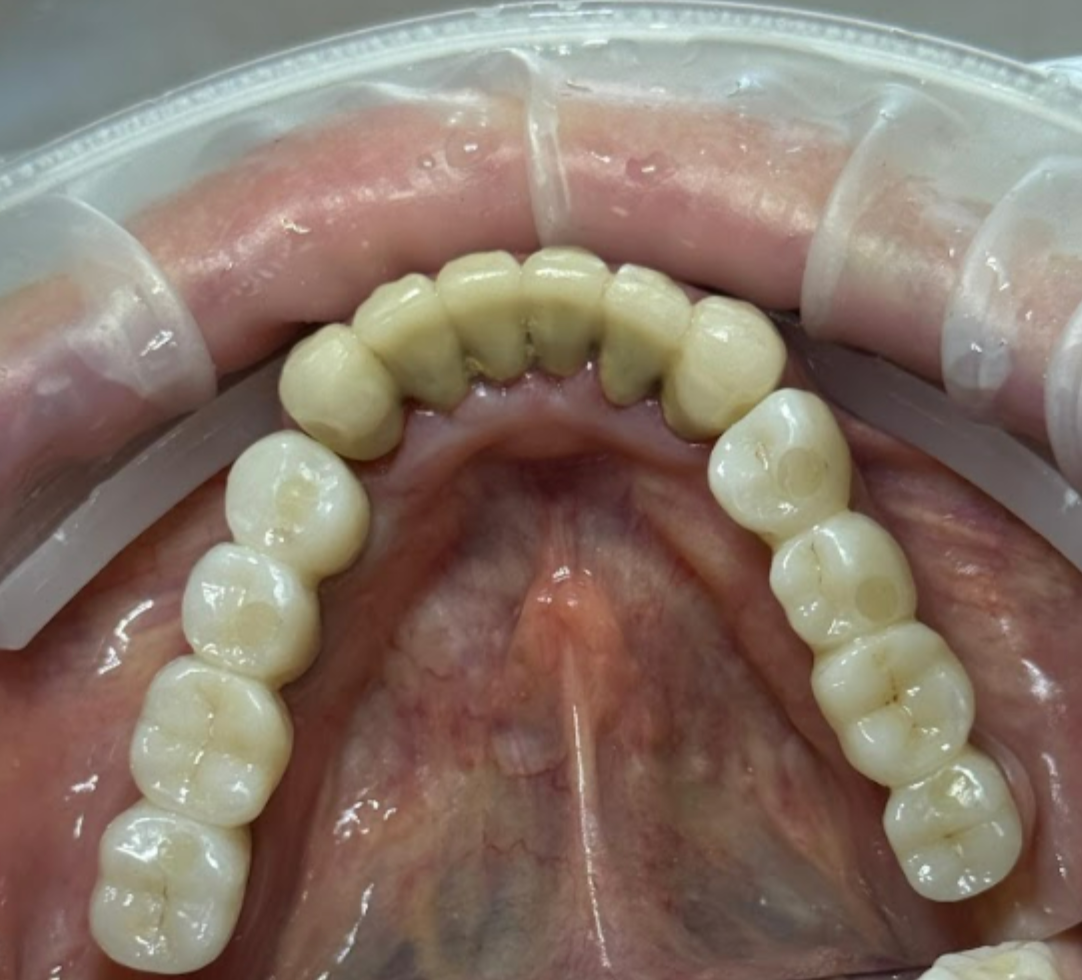

During the soft tissue healing and osseointegration period, the patient adhered to a soft diet. Upon complete healing and re-evaluation of all clinical parameters, zirconium dioxide bridges were fabricated and delivered.

The outcome is satisfactory from both functional and aesthetic perspectives.

The products selected for this screw-retained restoration include V-Type multi-unit abutments with various gingival heights for optimal soft tissue management.